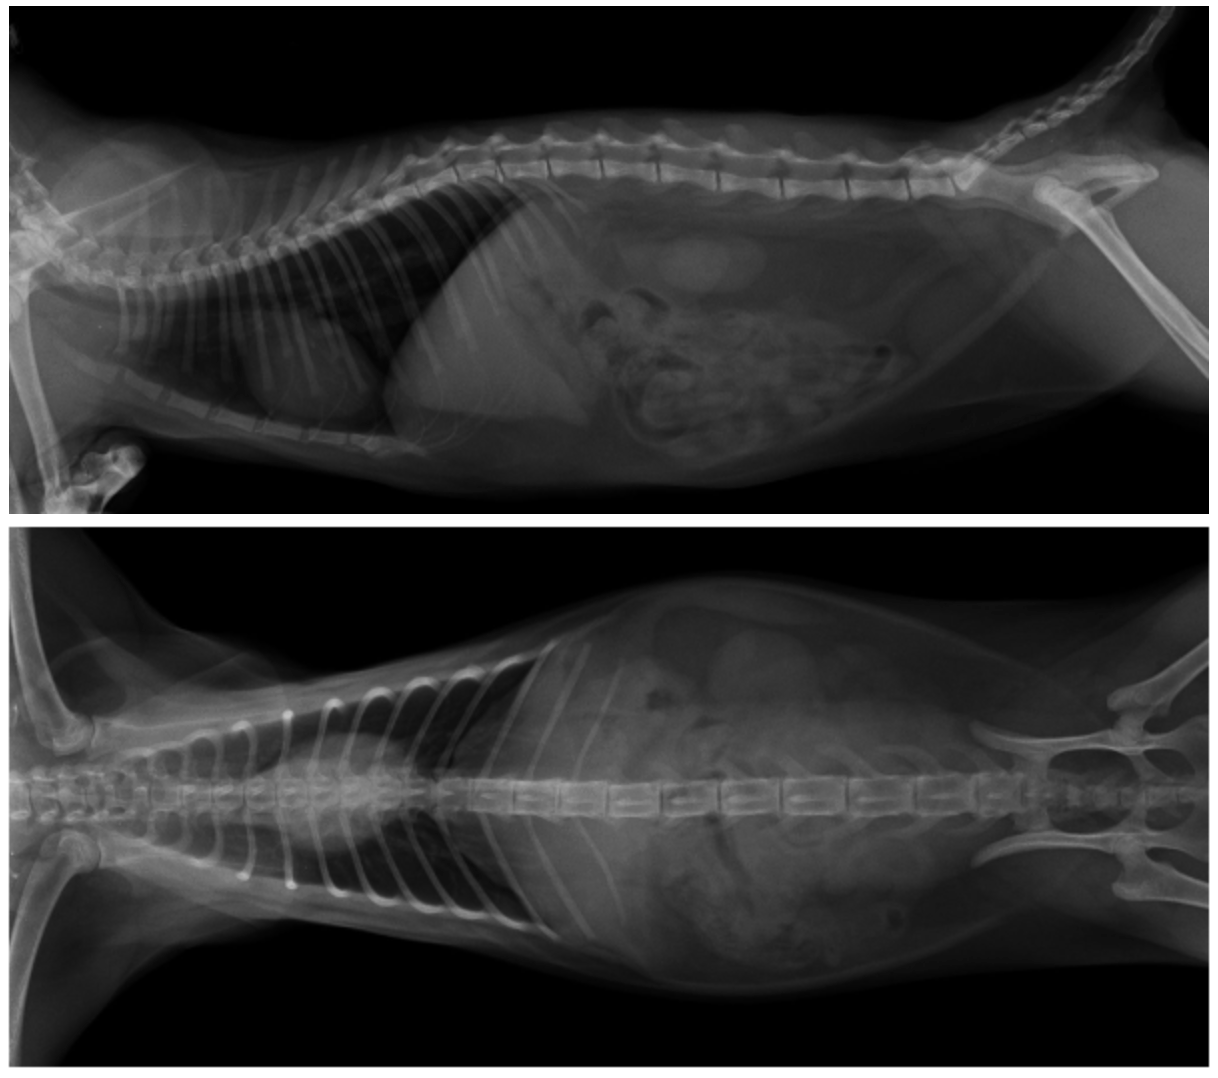

Feline spinal fractures

Abstract: In small animal clinical practice, spinal injury is a common cause of neurological dysfunction. Most common causes of spinal injury include disc herniation or dislocation, traffic accid...